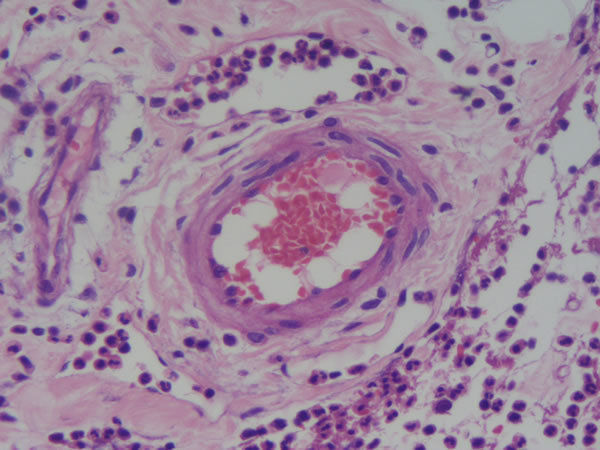

Pele - tec. pavim. estratif., conj. e tecido de granulação Reparo - Fístula cutânea Foco no tecido de granulação (novos vasos, muitas células de defesa) |

Pele - tec. pavim. estratif., conj. e tecido de granulação Reparo - Fístula cutânea Na parte de cima é o tecido já organizado/cicatrizado (mto fibroblasto) e na parte de baixo é tec. de granulação |